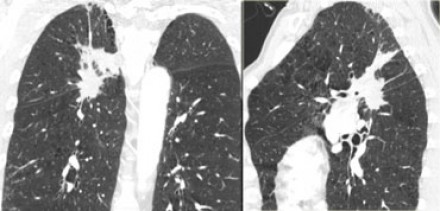

N1-стадия

|

|

N2 - стадия На данном снимке N2-стадия у пациента с ипсилатеральной медиастинальной

или субкаринной лимфаденопатией. |